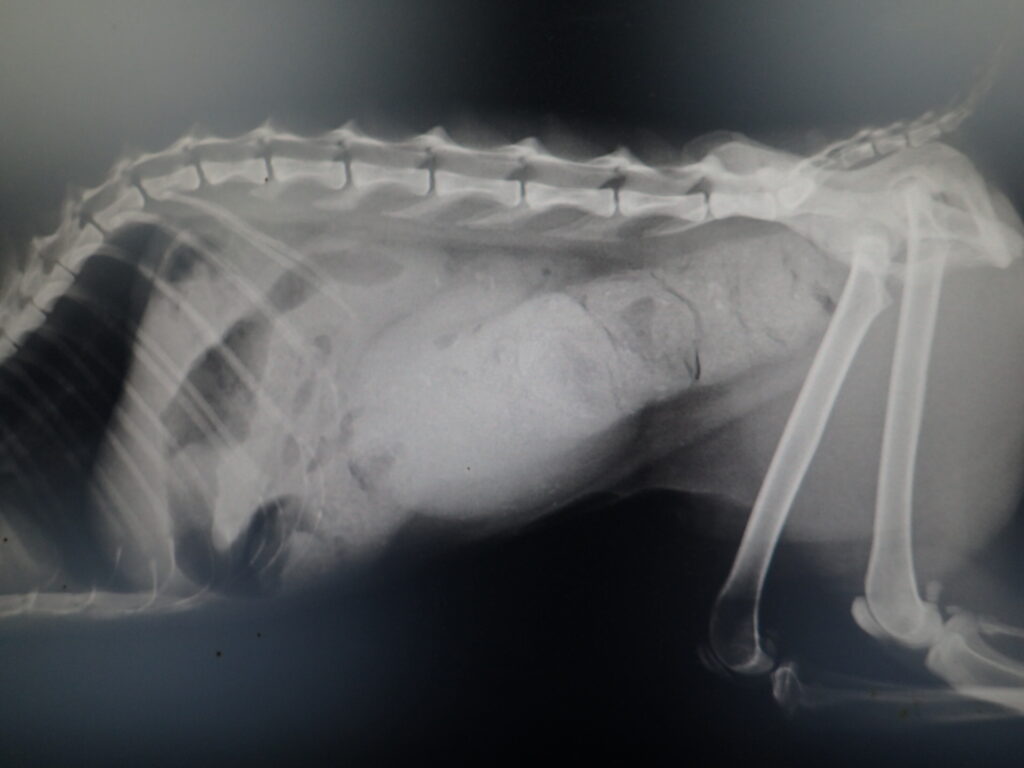

初期状態と症状

子猫の時の事故の影響で自力で排便排尿ができない。

毎日圧迫排尿し、定期的な浣腸にて排便させている。